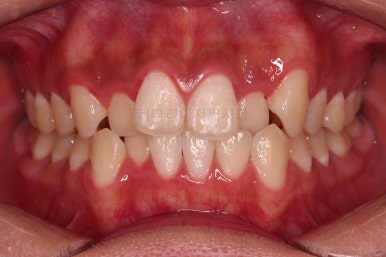

부산치아교정치과 초진 시 입안의 모습입니다.

앞니쪽이 위아래 모두 삐뚠 상태였고요.

왼쪽은 덧니로 툭 튀어나가 있고, 상대적으로 작은 앞니는 안으로 말려 들어가 아랫니와도 거꾸로 물리는 상태였습니다.